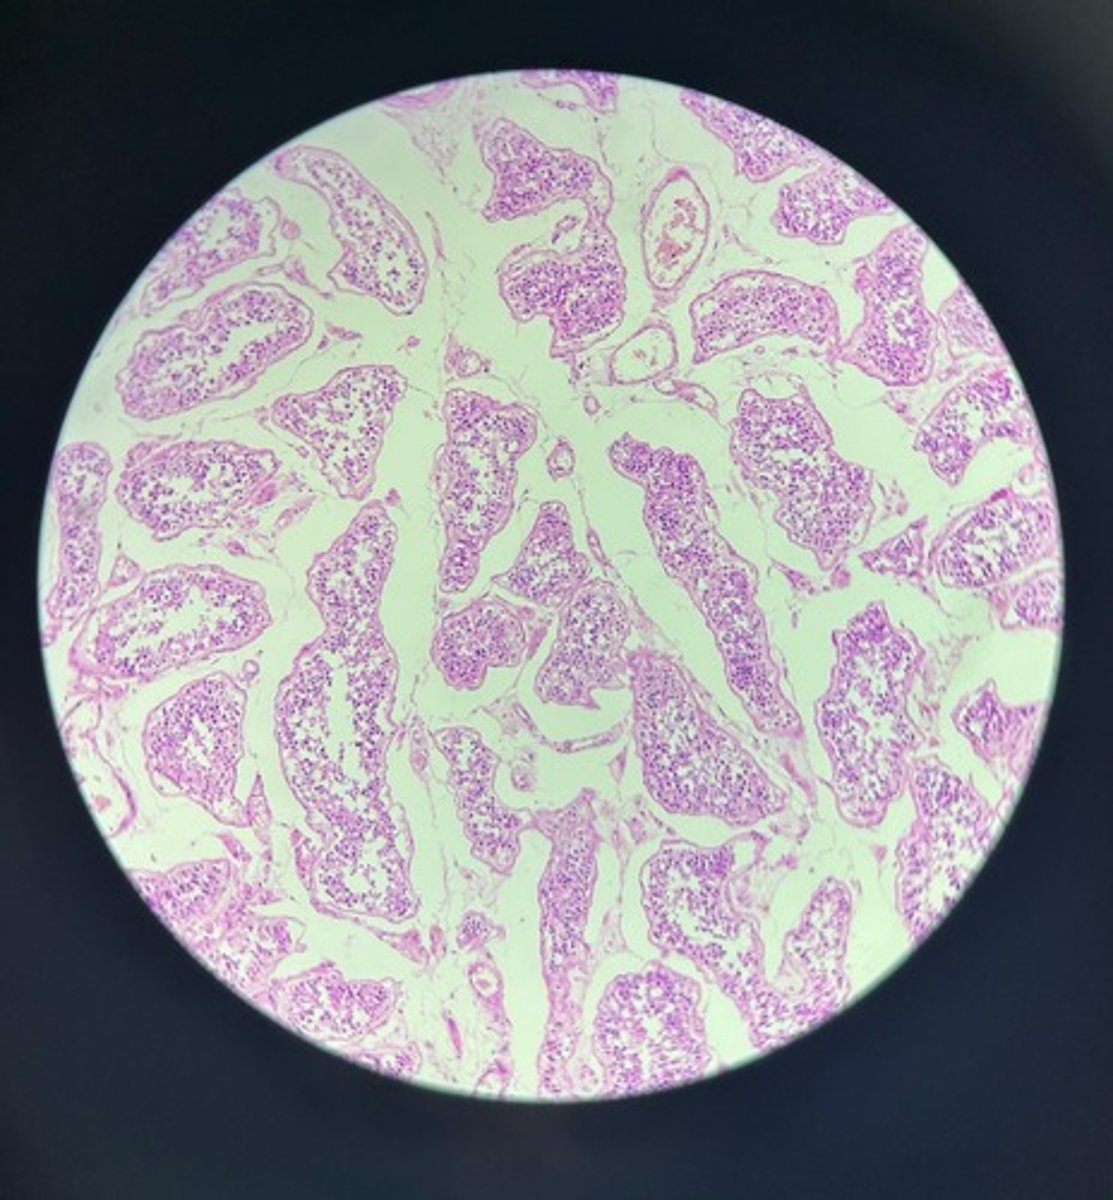

Testes HE

Testes HE

Testes HE

Testes HE

Testes HE